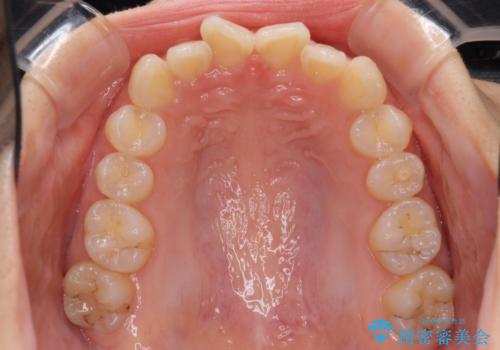

- 口元の深い咬み合わせ(ディープバイト)を気にして来院された患者様です。

インビザラインによる上下歯列の遠心移動(後方移動)により、口元のデコボコとディープバイトを改善することとしました。

下顎左右の犬歯とその後ろにある第一小臼歯、計4歯がシミュレーション通りに動かずディープバイトがなかなか改善されませんでした。

マウスピースの再製作を何度か行いましたがうまくいかないため、部分的にワイヤー矯正を併用することを提案しました。しかし、最も気になっていた前歯のデコボコはきれいに改善されたため、これ以上治療を希望されず、治療を終了することとしました。(今後気になった際には再開する予定です)